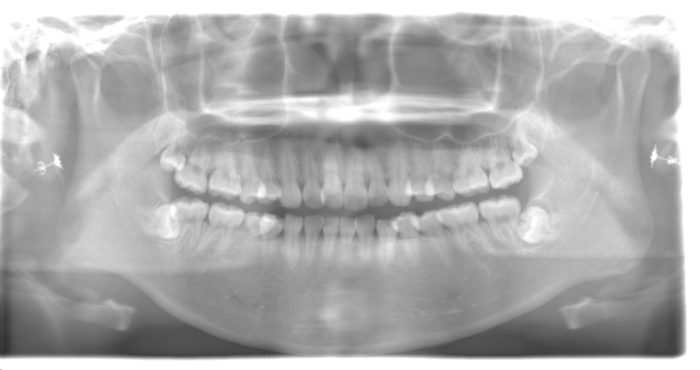

出っ歯(上顎前突)になりやすい理由

指をくわえると、上の前歯や上あごに常に前方向の力が加わります。その結果、前歯が徐々に前に傾き、口元が出て見える「出っ歯」になってしまうことがあります。

開咬(かいこう)のリスク

長期間指しゃぶりやおしゃぶりをしていると、前歯が上下で噛み合わずにすき間ができる「開咬」になることもあります。これにより、

- 前歯が大きく前に出ている

- 上下の前歯の間にすき間があり、噛み合わない

- 口を閉じにくく、いつも口が開いている